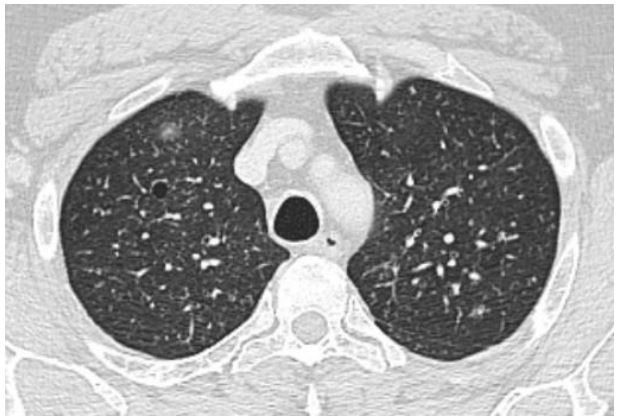

A 55-year-old man presented to an Internal Medicine physician after months of uncontrolled back pain despite of multiple therapies failure, asthenia, loss of weight and fever. Smoker, diagnosed of interstitial lung disease years ago, under follow-up by Pneumology and diagnostic doubts between bronchiolitis associated to tobacco smoking and pulmonary LCH, asymptomatic without specific treatment. Blood tests were unremarkable, with negative hepatitis serology and other infectious agents’ tests. Computer tomography of the chest showed centrilobular micronodules and cystic lesions in both lungs, with predilection for the mild and upper zones (Figure 1). These findings were consistent with the interstitial lung disease already known. A magnetic resonance of the spine showed multiple lytic bone lesions suggesting metastasis (Figure 2), so the study was completed with a PET scan that confirmed hypercaptation areas (Figure 3) in multiple vertebral bodies, scapula, pelvis, and costal arches.

Figure 2: Lytic bone lesions in spine RM.